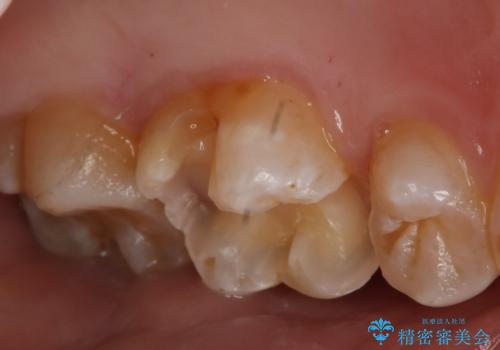

- 左上6番の銀歯のやり変えを希望し来院された患者様です。

切削量・形態を考慮し、セラミックインレーでの治療を計画しました。

銀歯直下のう蝕が深かったのでCRで裏層した上で形成、印象をしています。